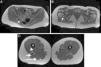

Magnetic resonance (MR) neurography refers to a set of techniques that enable the structure of the peripheral nerves and nerve plexuses to be evaluated optimally. New two-dimensional and three-dimensional neurographic sequences, in particular in 3T scanners, achieve excellent contrast between the nerve and perineural structures. MR neurography makes it possible to distinguish between the normal fascicular pattern of the nerve and anomalies like inflammation, trauma, and tumor that can affect nerves. In this article, we describe the structure of the sciatic nerve, its characteristics on MR neurography, and the most common diseases that affect it.